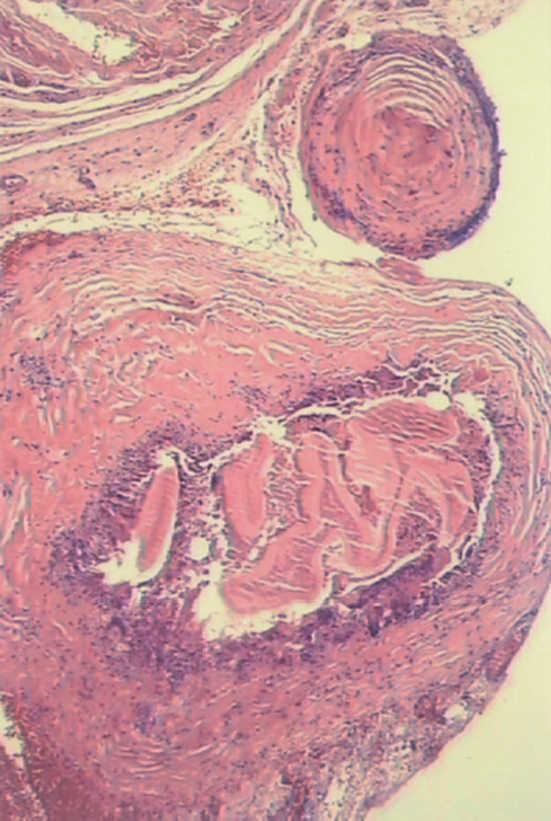

Se realizó intervención quirúrgica programada con PAIR (punción, aspiración, instilación intraquística de solución escolicida y reaspiración). En el estudio histológico se confirmó la presencia de restos de material necrótico y residuos de membranas hidatídicas rodeadas de intensa reacción inflamatoria de cuerpo extraño (fig. 3). Se administró tratamiento perioperatorio sinérgico con albendazol y praziquantel durante 16 semanas.

Figura 3. Anatomía patológica: membrana laminada de quiste hidatídico con intensa reacción fibrótica inflamatoria de cuerpo extraño de tipo granulomatoso crónico englobándole y tejido miopericárdico adyacente.